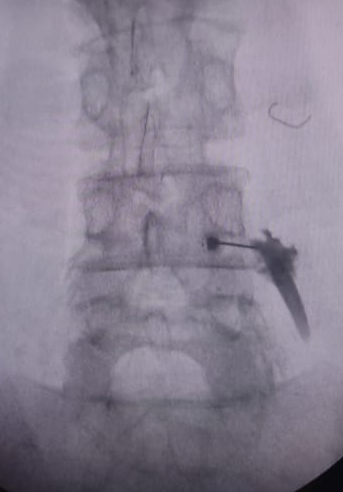

Now get your back & leg pain fixed with just a needle prick with Transforaminal Injection at the targeted level !! #Spineinjection #Transforaminalinjection #EpiduralInjection #Sciatica #Legpain